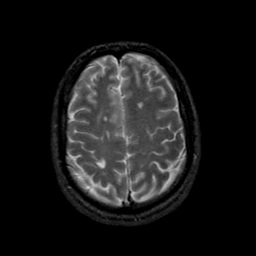

MR Study #23, January 26, 1992 -- Slice #38